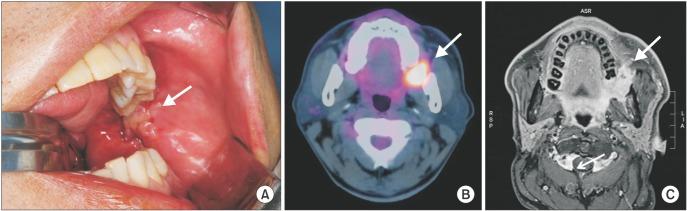

A surgical approach involving the retromolar trigone, posterolateral maxilla, and pterygoid region is the most challenging in the field of maxillofacial surgery. The upper cheek flap (Weber-Ferguson incision) with subciliary extension and the maxillary swing approach have been considered as alternatives; however, neither approach provides sufficient exposure of the pterygoid region and the anterior portion of the mandibular ramus. In this report, we describe two cases in which a lower cheek flap approach was used for complete tumor resection in the retromolar trigone and the anterior mandibular ramus. This approach allows full exposure of the posterolateral maxilla and the pterygoid region as well as the retromolar trigone without causing major sensory disturbances to the lower lip. A mental nerve anastomosis after tumor resection was performed in one patient and resulted in approximately 90% sensory recovery in the lower lip. The lower cheek flap approach provides adequate exposure of the posterolateral maxilla, including the pterygoid, retromolar trigone, and mandibular ramus areas. If the mental nerve can be anastomosed during flap approximation, postoperative sensory disturbances to the lower lip can be minimized.

涉及磨牙后三角、上颌骨后外侧和翼状区域的手术入路是颌面外科领域最具挑战性的。带有睑缘下延伸的上颊瓣(韦伯-弗格森切口)和上颌骨摆动入路已被视为替代方法;然而,这两种方法都不能充分暴露翼状区域和下颌支前部。在本报告中,我们描述了两例采用下颊瓣入路进行磨牙后三角和下颌支前部肿瘤完整切除的病例。这种入路可充分暴露上颌骨后外侧和翼状区域以及磨牙后三角,且不会对下唇造成严重感觉障碍。一名患者在肿瘤切除后进行了颏神经吻合术,下唇感觉恢复约90%。下颊瓣入路可充分暴露上颌骨后外侧,包括翼状、磨牙后三角和下颌支区域。如果在瓣片贴合时能进行颏神经吻合,可将术后下唇感觉障碍降至最低。